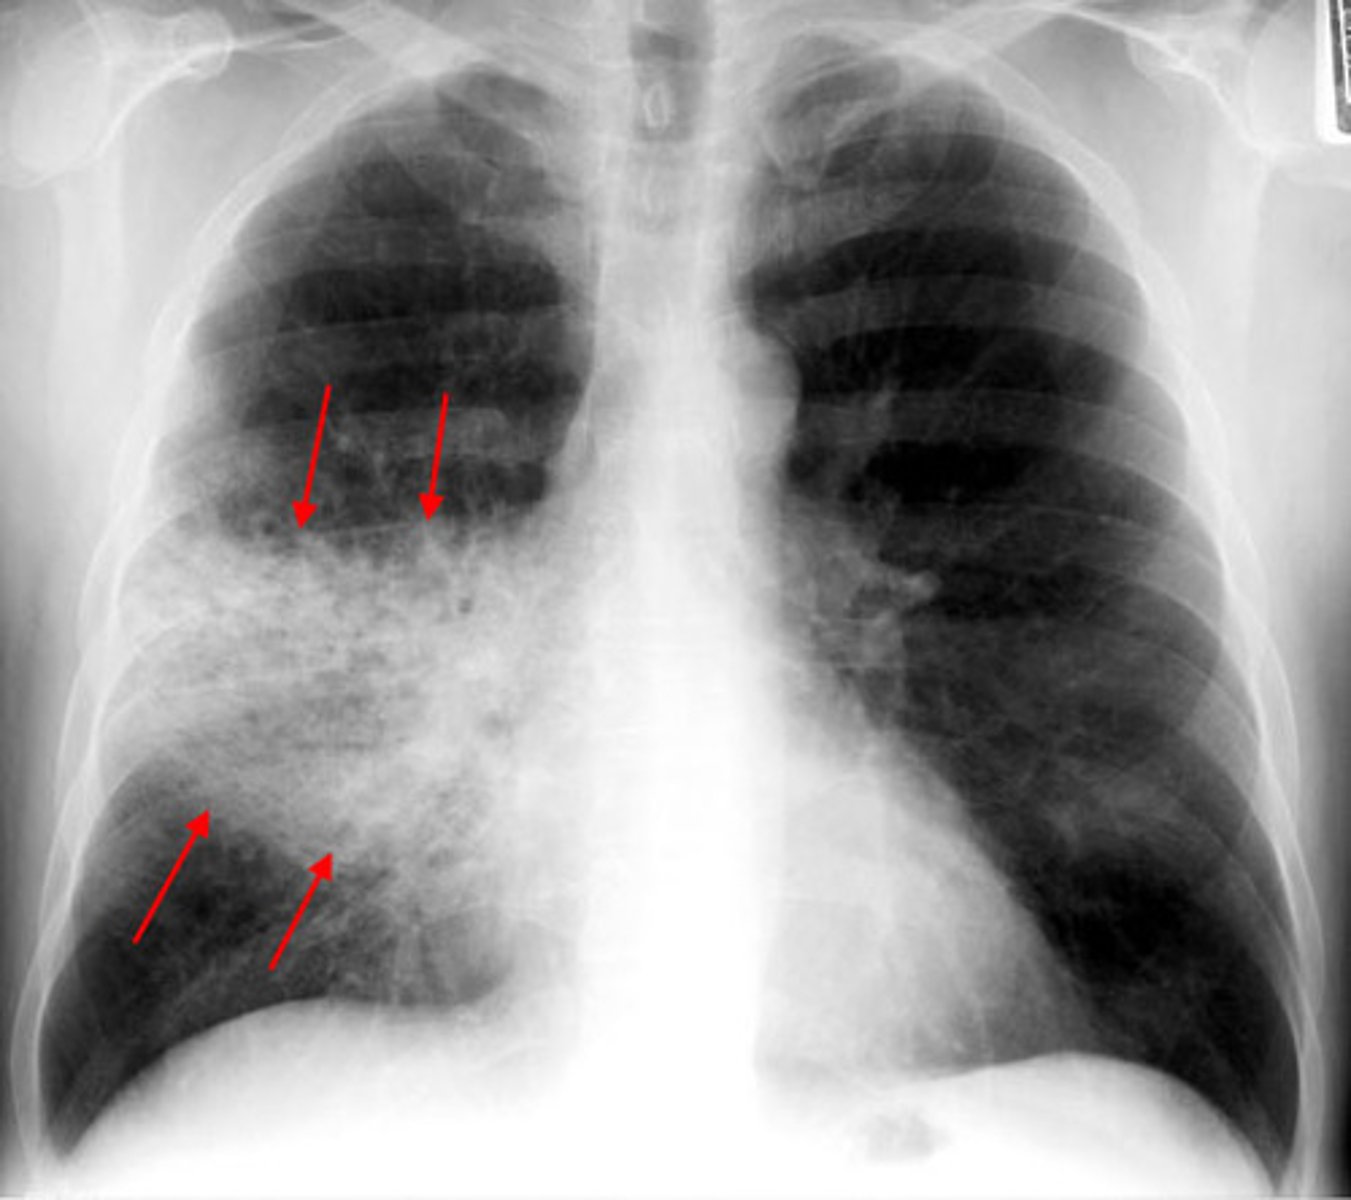

Typical Pneumonia

Pathogen: Streptococcus pneumoniae

S+S: Inflammation of the alveoli in one or both lungs --> Rapid onset of chest pain, dyspnea, high fever, productive cough

X-Ray: Looks equal to S+S severity - lobar involvement

Atypical (walking) Pneumonia

Pathogen: Mycoplasma pneumoniae

S+S: Inflammation of the alveoli in one or both lungs --> Slow onset of dry cough and mild fever, NO chest pain/dyspnea

X-Ray: Look worse than symptoms - interstitial involvement